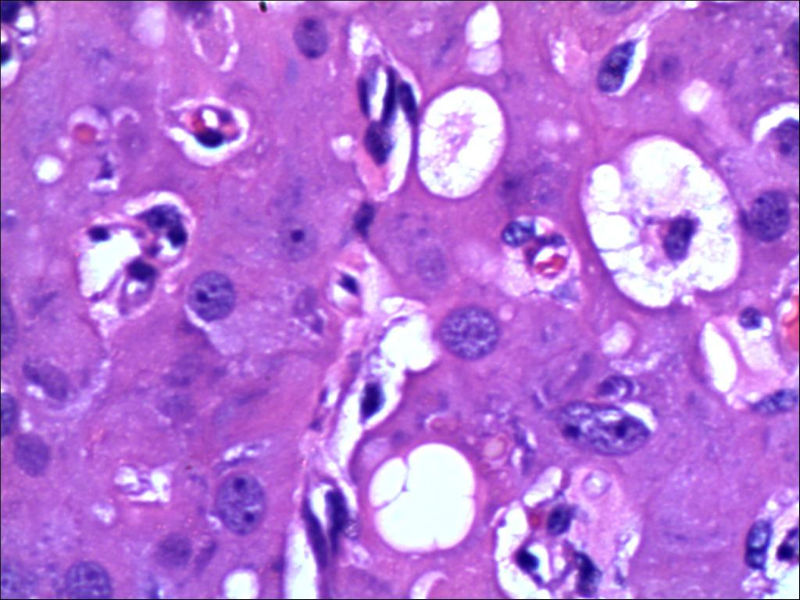

女,27岁,送检右侧卵巢肿物(另外还送检左侧卵巢肿物,大体及镜下显示为畸胎瘤),卵圆形,大小2×1×1cm,似有包膜。卵巢肿物图1

卵巢畸胎瘤中正常卵巢的黄体组织,铺砖样排列,胞浆宽大,较典型。

不好意思,可能是我没说清楚,患者对侧卵巢是畸胎瘤,不是同一侧的,我初步考虑门细胞瘤,图21,22,24,25,26中央的一些细胞是不是很像门细胞

谢谢大家的回答和解疑,忘记一个重要的病史,就是该女性为产妇。但是妊娠黄体瘤与类固醇细胞瘤怎么鉴别呢

那应该是妊娠黄体/黄体瘤,类固醇细胞瘤有嗜酸细胞和组织细胞样细胞两种,此例显然不是。